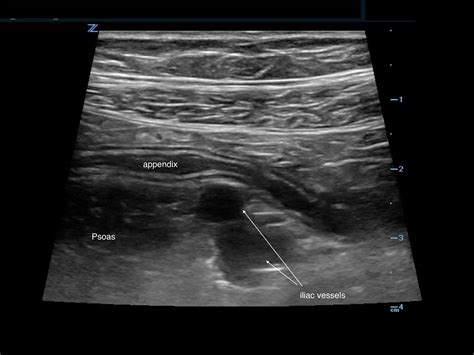

When performing an ultrasound to diagnose appendicitis, radiologists look for several key signs:

• Appendiceal Diameter: A normal appendix is typically less than 6 mm in diameter. An inflamed appendix will often be larger than 6 mm.

• Appendiceal Wall Thickness: The wall of the inflamed appendix may appear thicker than normal.

• Probe Placement: The ultrasound probe is placed on the right lower quadrant of the abdomen, where the appendix is located.

• Image Acquisition: The radiologist moves the probe to capture images of the appendix from different angles. Doppler ultrasound may be used to assess blood flow.

• Interpretation: The images are reviewed to look for the signs of appendicitis mentioned earlier.